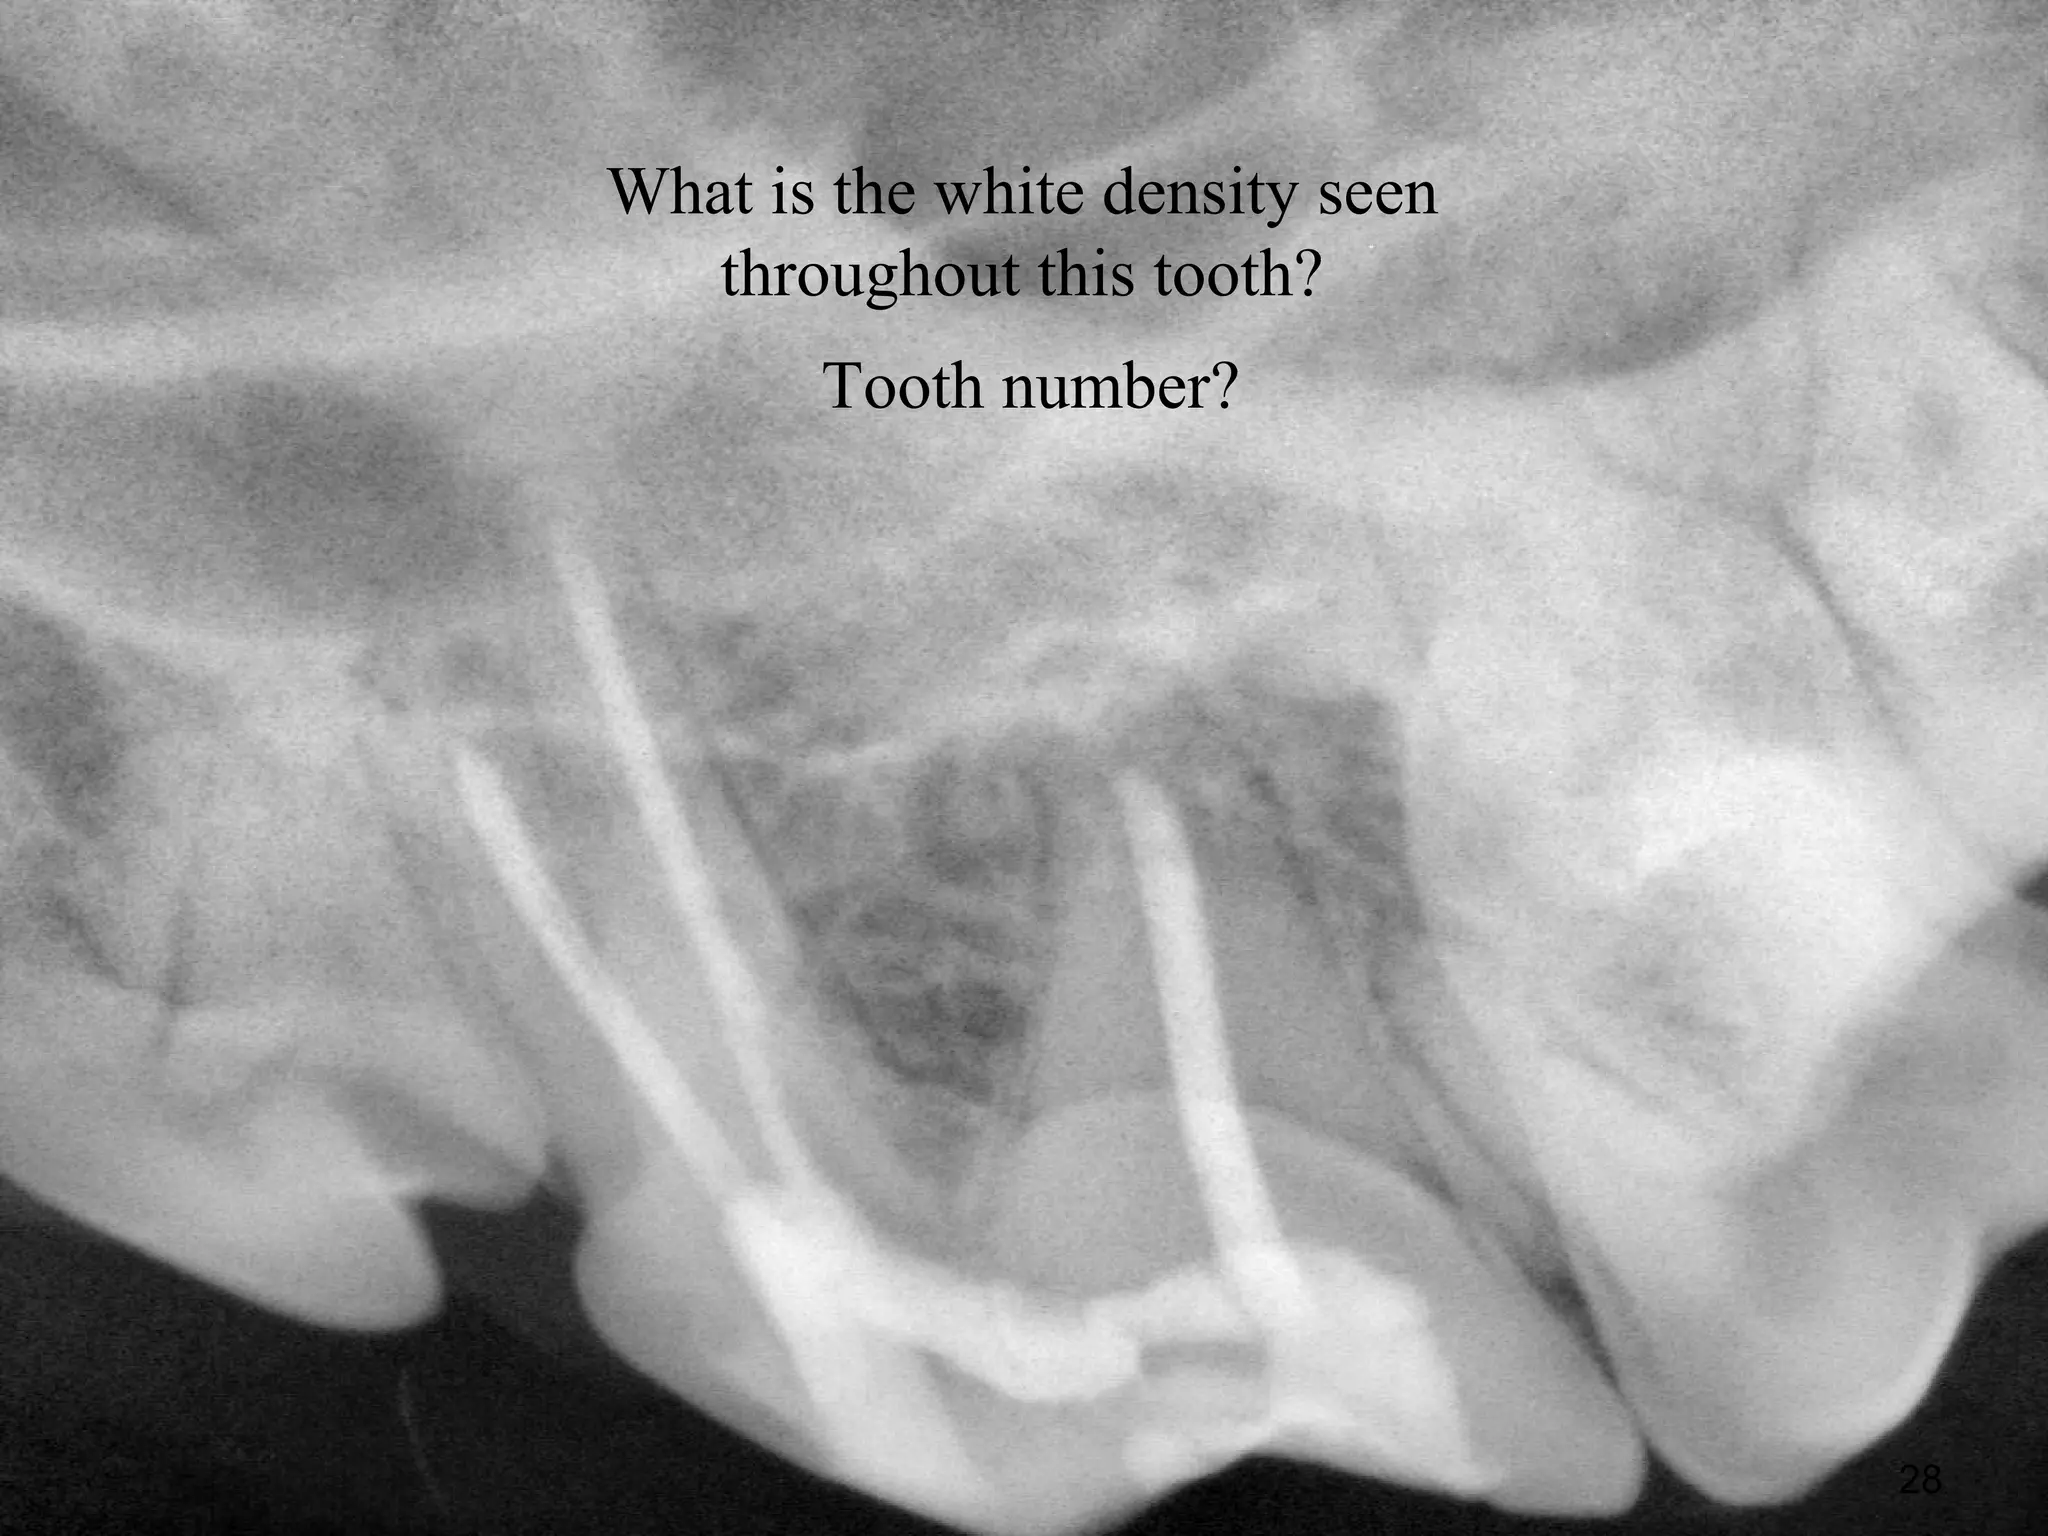

What is the white density seen

throughout this tooth?

Tooth number?

28

What is thewhite density seen throughout this tooth? Tooth number? 28